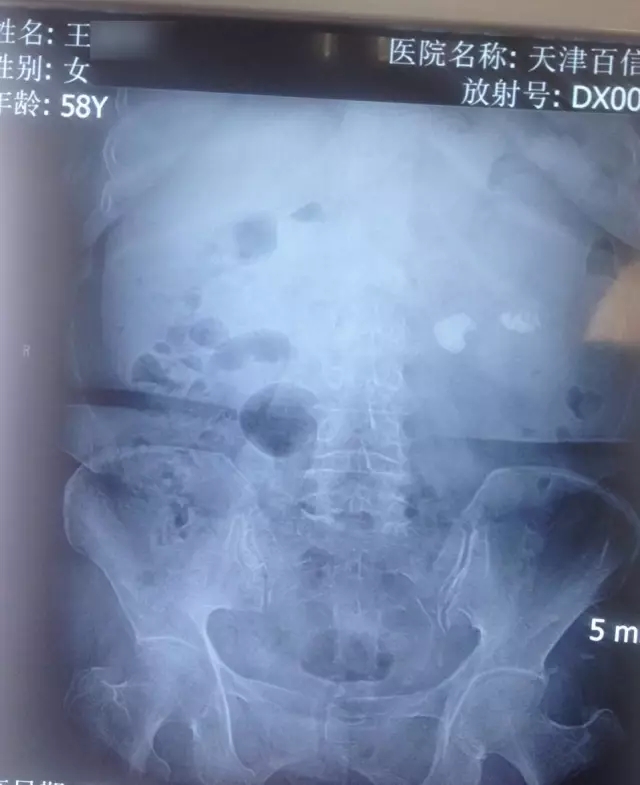

姓名:王女士

年龄:58岁

病症表现:患肾结石10年,腹部剧烈疼痛、血尿

诊断结果:左肾结石

手术方案:经皮肾镜碎石取石术

其他描述:患者患肾结石10年,曾多次体外碎石,效果不理想,反复发作。入院检查显示,患者左肾布满大小不一的结石,而且最大的直径约1.7厘米位于左肾肾盂输尿管移行处。李月明主任为患者进行经皮肾镜碎石取石术,取出患者左肾内结石,术后检查显示,取净率100%,接触患者10年困扰。